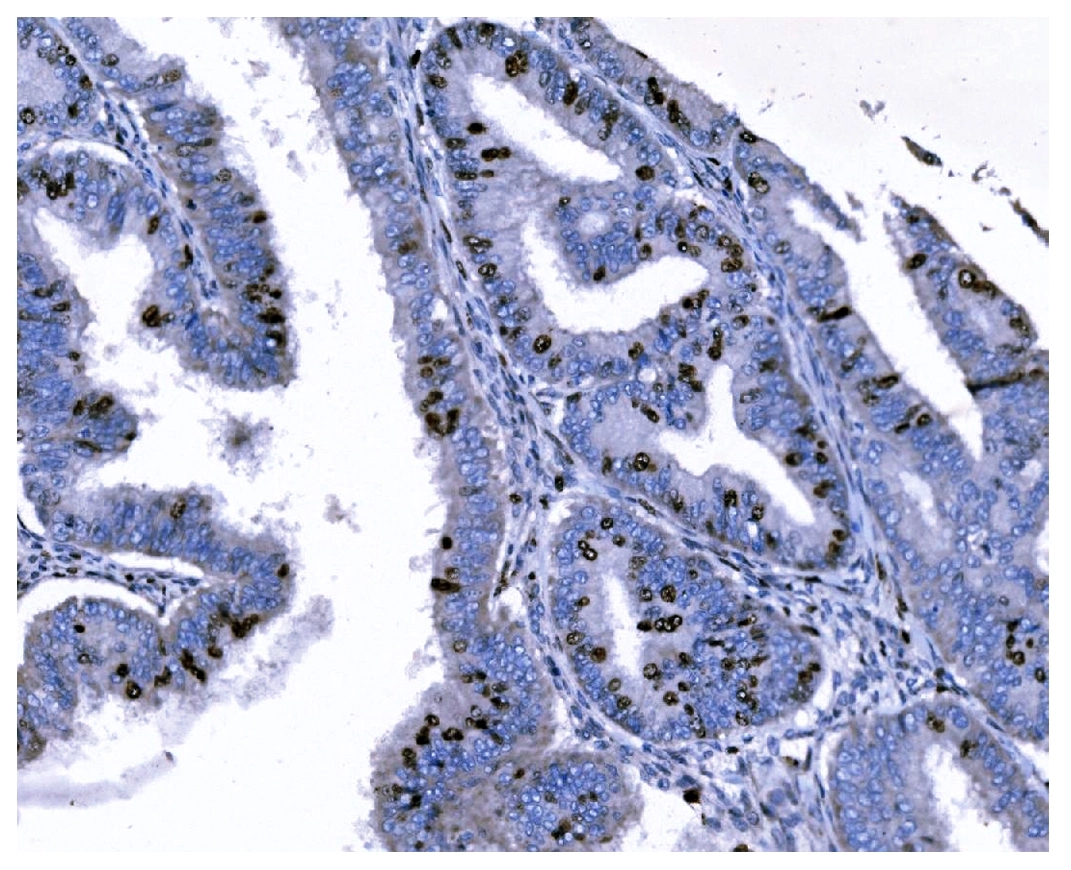

IHC analysis of Ki67/MKI67 using anti-Ki67/MKI67 antibody (M00254-9).

Ki67/MKI67 was detected in a paraffin-embedded section of human lymphomas tissue. Biotinylated goat anti-mouse IgG was used as secondary antibody. The tissue section was incubated with mouse anti-Ki67/MKI67 Antibody (M00254-9) at a dilution of 1:200 and developed using Strepavidin-Biotin-Complex (SABC) (Catalog # SA1021) with DAB (Catalog # AR1027) as the chromogen.